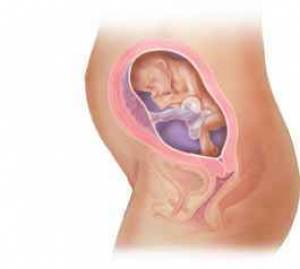

بارداری هفته به هفته و تغییر وضعیت جنین+عکس

بارداری معمولا 280 روز یا 40 هفته بطول می انجامد، که بطور قراردادی از اولین روز آخرین قاعدگی شروع می شود. این دوران را می توان به سه "سه ماهه" بارداری تقسیم کرد که در هر یک وقایع خاصی اتفاق می افتد؛ سه ماهه اول از اولین هفته بارداری تا انتهای هفته 13، سه ماهه دوم از هفته 14 تا پایان هفته 27، و سه ماهه سوم از هفته 28 تا آخر هفته 40 است که عمدتا در این زمان (کمی زودتر یا دیرتر) به زایمان و تولد نوزاد ختم می شود.

هر سه ماهه مشخصات مربوط به خود را دارد؛ در سه ماهه اول ضربان قلب جنین شنیده می شود، در سه ماهه دوم اولین حرکات جنین توسط مادر احساس می شود، و در سه ماهه آخر برخی از مادران انقباضات کاذب زایمانی موسوم به برکستون- هیکز را تجربه می کنند. بعضی از آزمایشات مانند نمونه برداری از پرزهای جفتی در سه ماهه اول و آمنیوسنتز در سه ماهه دوم انجام می شوند. برخی از مسائل مانند دیابت بارداری، در سه ماهه آخر تظاهر می کنند. در این دوران عواطف و احساسات شما نیز مانند بدنتان دستخوش تغییراتی می شود و شرایط زندگی برای خانواده بتدریج آماده پذیرایی از کودک آینده خواهد شد.